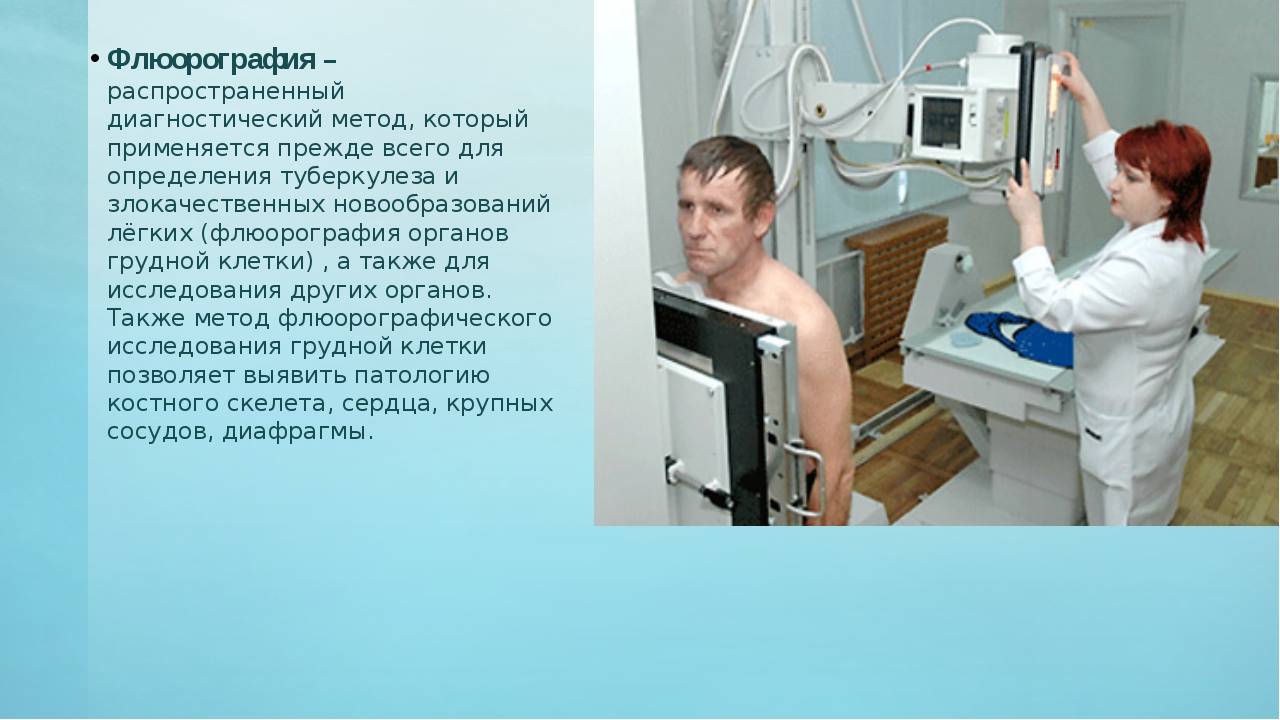

Влияние излучения при флюорографии: что нужно знать?